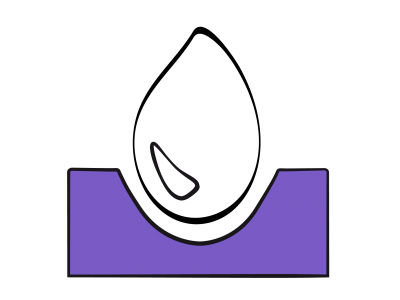

Il n'existe aucune mesure directe de la volémie utilisable en clinique. On se réfère habituellement à la détermination de valeurs de substitution, telles la pression artérielle ou la pression veineuse centrale (PVC). Or la pression et le volume de remplissage sont reliés entre eux par la compliance de la cavité cardiaque. Cette relation est curvilinéaire : les variations de pression (ΔP) sont minimes par rapport aux variations de volume (ΔV) à bas volume de remplissage parce que la courbe de compliance est quasi-horizontale en hypovolémie, mais importantes à haut volume parce que la courbe se redresse (Figure 27.1) [10]. De ce fait, la corrélation de la PVC à la volémie est inexistante lorsque la précharge est basse (r = 0.3-0.5) [22].

Figure 27.1 : Courbe de compliance du ventricule. La courbe normale (en bleu) est curvilinéaire. En hypervolémie, une variation du volume de remplissage (ΔV) se traduit par une variation significative de la pression télédiastolique (PVC ou PAPO) parce que la courbe est bien redressée. En hypovolémie, au contraire, la courbe est très plate, et une variation de volume (ΔV') même importante ne provoque qu'une modification minime, voir non mesurable, de la pression de remplissage (ΔP'). Ce phénomène invalide la mesure de la PVC ou de la PAPO comme indice d'hypovolémie. En cas de dysfonction diastolique, la courbe de compliance (en rouge) est déplacée vers le haut (la pression de remplissage est plus élevée pour le même volume) et redressée dès son origine.

Il n'existe aucune mesure directe de la volémie utilisable en clinique. On se réfère habituellement à la détermination de valeurs de substitution, telles la pression artérielle ou la pression veineuse centrale (PVC). Or la pression et le volume de remplissage sont reliés entre eux par la compliance de la cavité cardiaque. Cette relation est curvilinéaire : les variations de pression (ΔP) sont minimes par rapport aux variations de volume (ΔV) à bas volume de remplissage parce que la courbe de compliance est quasi-horizontale en hypovolémie, mais importantes à haut volume parce que la courbe se redresse (Figure 27.1) [10]. De ce fait, la corrélation de la PVC à la volémie est inexistante lorsque la précharge est basse (r = 0.3-0.5) [22].

Figure 27.1 : Courbe de compliance du ventricule. La courbe normale (en bleu) est curvilinéaire. En hypervolémie, une variation du volume de remplissage (ΔV) se traduit par une variation significative de la pression télédiastolique (PVC ou PAPO) parce que la courbe est bien redressée. En hypovolémie, au contraire, la courbe est très plate, et une variation de volume (ΔV') même importante ne provoque qu'une modification minime, voir non mesurable, de la pression de remplissage (ΔP'). Ce phénomène invalide la mesure de la PVC ou de la PAPO comme indice d'hypovolémie. En cas de dysfonction diastolique, la courbe de compliance (en rouge) est déplacée vers le haut (la pression de remplissage est plus élevée pour le même volume) et redressée dès son origine.